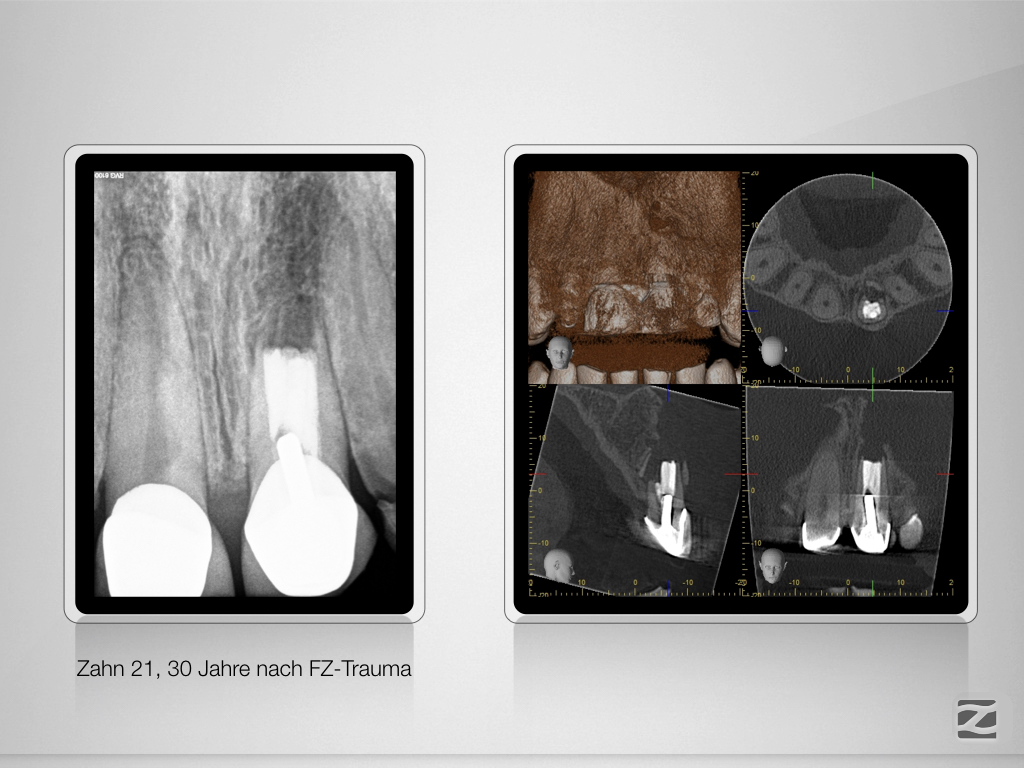

DVT & Ex.001

Entscheidungshilfe